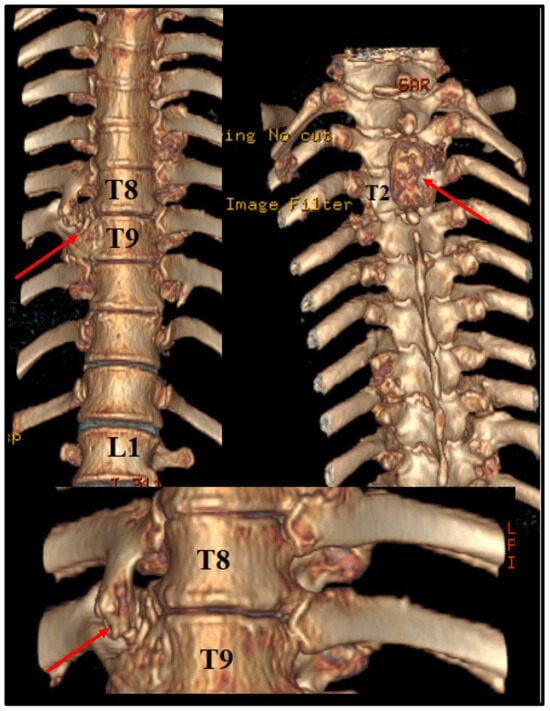

Before the intervention, we asked for a 3D CT reconstruction, which helped to appreciate the exterior aspect of the vertebral column, as well as to acknowledge the outer extensions of the exostosis (Figure 2).

Figure 2. Preoperative 3D CT scan. Note the outer margins of the osteochondroma, along with another one, localized at T2 level, which was neurologically silent.